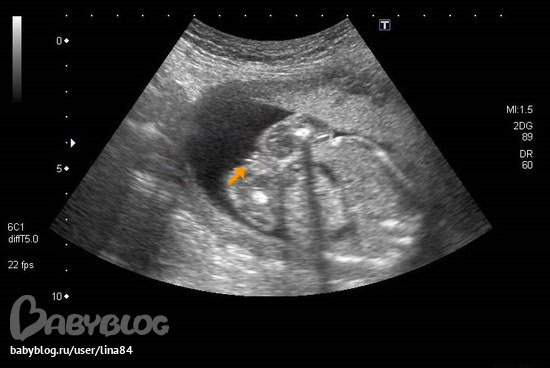

Вопросы про УЗИ, обследования и анализы: что, где, как, когда?Яне могу успокоится,начиталась про ошибки узистов в определении пола. Вот снимок нашей 100%доченьки,как узистка сказала. Девочки,это точно пирожок?....

у девочек половые губы большие на узи с яичками легко перепутать можно...

Однозначно девочка. Если бы мальчик там бы еще по серединке торчало бы чего-нибудь. Я то уж знаю.